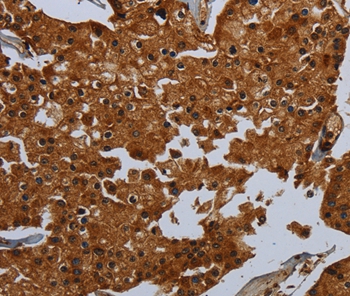

图片:

Immunohistochemical analysis of paraffin-embedded Human prostate cancer tissue using #36615 at dilution 1/60.

Immunohistochemical analysis of paraffin-embedded Human brain tissue using #36615 at dilution 1/60.